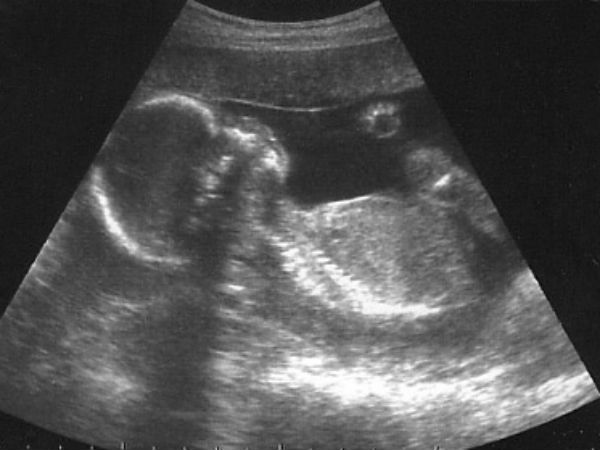

பெய்ஜிங்: சீனாவில் ஒரு பெண்ணின் கருவில் இருந்த குழந்தை உதைத்ததால் அவரின் வயிறு கிழிந்து சிறிய அளவில் துளை ஒன்று ஏற்பட்டுள்ளது. குழந்தை உதைத்த வேகம் அதிகமாகி அதிகமாகி திடீரென கட்டுப்படுத்த முடியாத நிலைமைக்கு சென்றுள்ளது. கருவில் இருந்த குழந்தையின் இந்த உதை காரணமாக வயிற்றில் சிறிய அளவில் துளை ஒன்று உருவாகி இருக்கிறது. இந்த விஷயம் அந்தப் பகுதியில் பெரும் பரபரப்பை ஏற்படுத்தியுள்ளது.

இது போன்று கர்ப்பமாக இருந்த சீனாவைச் சேர்ந்த ஷாங்க் என்ற பெண்ணின் வாழ்க்கையில் ஒரு விசித்திரமான சம்பவம் நடந்துள்ளது. 35 வயது நிரம்பிய இவர் நிறைமாத கர்பிணி ஆவார். இவருக்கு கடந்த சில நாட்களாக வயிற்றில் மிகவும் அதிக அளவில் வலி இருந்திருக்கிறது.

அதன்பின் கடந்த மூன்று நாட்களாக வலி சிறிது சிறிதாக அதிகரித்துள்ளது. மேலும் வயிற்றில் குழந்தை உதைத்த வேகமும் அதிகரித்துள்ளது. இந்த நிலையில் குழந்தை வேகமாக உதைத்ததில் அந்தப் பெண்ணின் வயிற்றில் சிறிய அளவில் துளை விழுந்துள்ளது. இதையடுத்து வயிற்றில் இருந்து அதிக அளவில் ரத்தம் வெளிவர தொடங்கி இருக்கிறது.

இதையடுத்து அவர் மருத்துவமனைக்கு அவசரமாக கொண்டு செல்லப்பட்டார். சில ஆண்டுகளுக்கு முன் வயிற்றில் சிறுநீர் பை நீக்கத்திற்காக இவர் செய்த ஆப்ரேஷனால் , வயிற்றின் சில பகுதிகள் வலிமை இல்லாமல் இருந்திருக்கிறது. இதையடுத்தே குழந்தை உதைத்தவுடன் வயிற்றில் துளை உருவாகியிருக்கிறது என்று கூறப்படுகிறது.